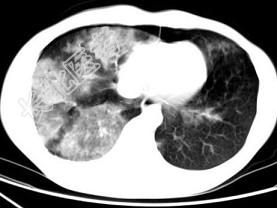

- 单项选择题男,28岁, 外伤后1小时,胸部CT如图, 最可能的诊断为 ( )

A、肺炎

B、肺脓肿

C、肺囊肿

D、肺癌

E、双肺挫伤